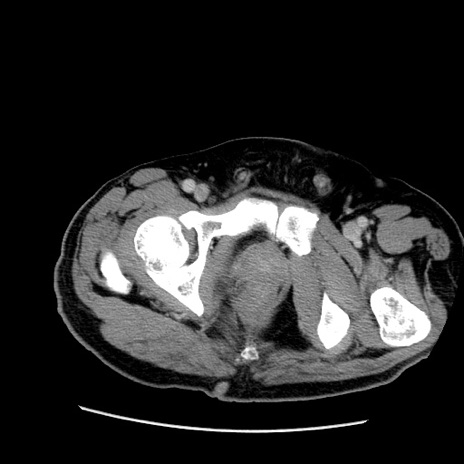

症例22(横断像)

【症例】50歳代男性

【主訴】腹痛

【現病歴】AVMからの被殻出血のため回復期リハ病棟入院中。 本日午後3時頃急に下腹部痛が出現した。

【既往歴】AVM、被殻出血、虫垂炎、高血圧

【身体所見】意識晴明、左半身不全麻痺、会話の理解は良好、36.5°C、腹部:膨隆、全体に板状硬、下腹部正中に圧痛点あり、反跳痛-、筋性防御不明、右下腹部にope scar

【データ】WBC 9400、CRP 0.06